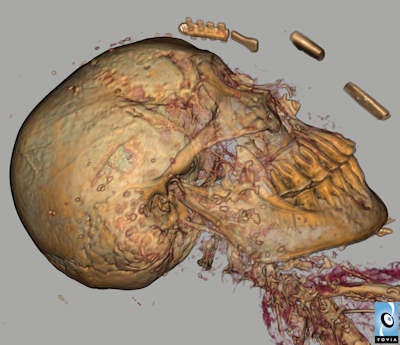

Using a 320-slice CT scanner (Aquilion One, Toshiba Medical Systems Europe), van Beek and colleagues performed 0.25 mm volumetric imaging using two kV settings and using maximal mAs. Additional imaging of the head was performed, using a gantry tilt to allow for better reconstruction of the head and facial bones.

Martin Connell, a clinical scientist at the Clinical Imaging Research Centre, did the initial 3D reconstruction using Voxar 3D visualization software. Dr. Saeed Mirsadraee, a senior clinical lecturer in radiology at the University of Edinburgh, did subsequent image postprocessing.

A metal amulet showing a flying scarab was identified on the woman's forehead, presumably made of pure gold. The exhibition contains a replicate of this. Several other amulets were identified, on and within the linen wrappings.

Most exciting was the discovery that a scroll, presumably a funerary text made of papyrus containing the mummy's lineage or name, directions for mummification, and guidance for the afterlife, had been placed in her right hand resting on a thigh."We were able to reconstruct the dimensions and the position of the scroll, and we are having discussions as to whether micro-CT may be able to make this legible," van Beek said. A team of specialists from Toshiba Medical Visualization Systems Europe performed the scroll reconstruction.